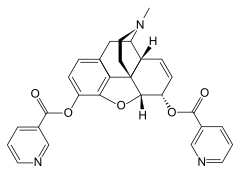

- Esters of morphine opiates: slightly chemically altered but more natural than the semi-synthetics, as most are morphine prodrugs, diacetylmorphine (morphine diacetate; heroin), nicomorphine (morphine dinicotinate), dipropanoylmorphine (morphine dipropionate), desomorphine, acetylpropionylmorphine, dibenzoylmorphine, diacetyldihydromorphine;[261][262]